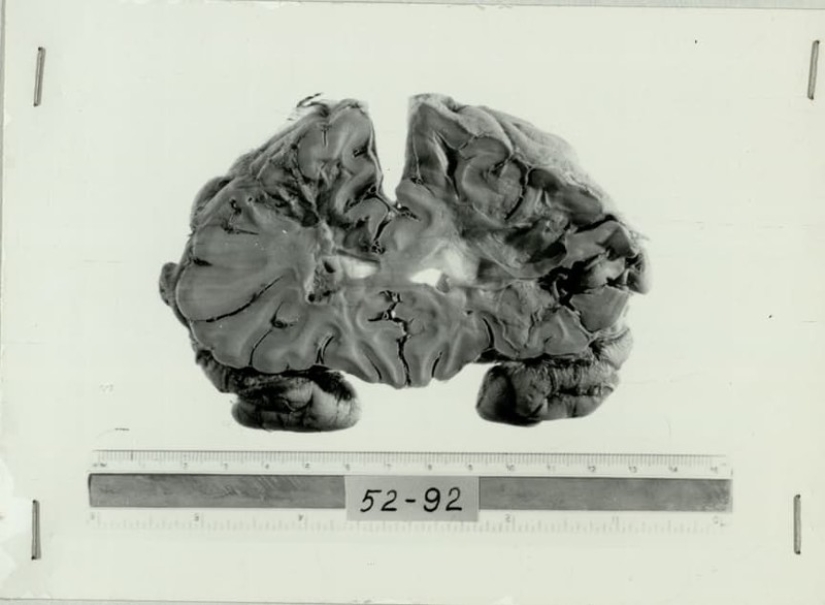

La lobotomía o lakatamia llamado de la operación, durante la cual intencionalmente heridos o han escalas lóbulo frontal del cerebro. Intencionalmente infligidas defecto cerebral rompió la conexión de los lóbulos frontales con el resto del cerebro. El médico inyecta el cuchillo a través de la cuenca del ojo del paciente, actuando casi a ciegas. El éxito de la operación dependía de la habilidad del cirujano, su conocimiento de la anatomía del cerebro.

Permantaly corteza completa 20 años. La función de esta parte de la materia gris que nos hacen individuales. Los lóbulos frontales proveer la coordinación, la concentración, la planificación, la gestión de las emociones. El conjunto de todas las funciones de la corteza prefrontal, que crea nuestra personalidad. La implicación era que la lobotomía se apaga esta área del cerebro, evitando que el paciente, la ansiedad, la irritabilidad, la agresividad.